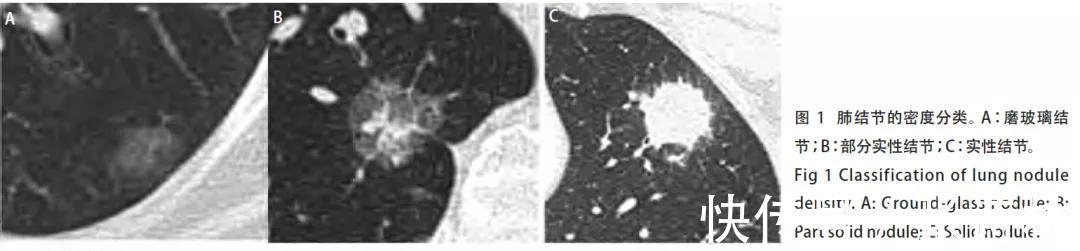

实性结节(solid nodule)——恶性概率较低。实性结节是指其内全部是软组织密度的结节,密度较均匀,其内血管及支气管影像被掩盖。